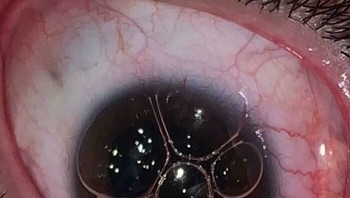

Rambut Tumbuh Di Mata Foto: Boredpanda